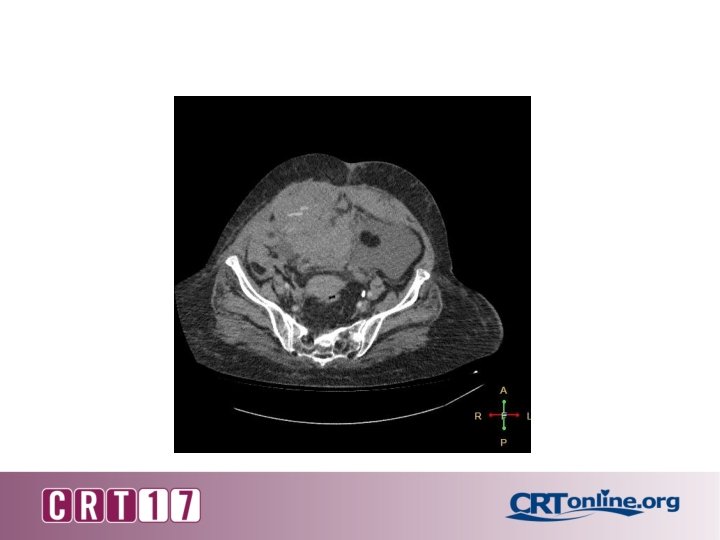

• Abdominal CT with contrast revealed type III rectus sheath haematoma extending into pelvis with active bleeding into haematoma.

Type III rectus sheath hematoma extending into pelvis with disruption of rectus sheath inferiorly.

Imaging study